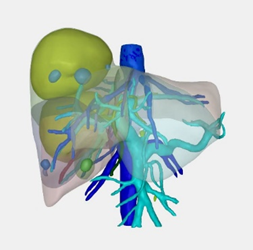

术前三维可视化分析

经术前三维成像评估右半肝切除后残肝体积为标准肝体积的50%,但吲哚箐绿(ICG)15分钟滞留率(ICG-R15)达25%,暂停手术,于是加强营养支持治疗,一周后复查ICG15分钟滞留率为14%,最后经肝胆胰外科专家组讨论不符合腹腔镜肝切除要求,决定行前入路右半肝切除术。右上腹斜切口进腹,探查见肝脏呈轻度肝硬化,两个肿瘤直径接近10.0cm的巨大肿瘤占据半肝,一个于包膜外可见,一个位于肝实质内,周围数个微小结节,未见肝内转移灶和腹腔转移灶,为避免术中不适当挤压引起肿瘤经血管转移和肿瘤破裂,先切断肝圆韧带和肝镰状韧带,解剖第二肝门,显露肝右和肝中静脉窝,然后切除胆囊,解剖第一肝门,鞘外分离右肝蒂,预阻断后见右肝缺血明显,除一个微小结节略偏向S4段外,肿瘤全部位于右肝缺血线内,于缺血性和S4段结节稍左侧约1.0cm画切肝线,术中超声证实肝中静脉位于切线下方、全部肿瘤位于切线右侧,结扎右肝蒂,以15+5min模式间歇性阻断肝门,原位离断左右肝之间肝实质,结扎切断肝断面血管和胆管,到达右肝蒂时确认右肝蒂后右切割闭合器离断右肝蒂,继续沿中肝静脉右侧离断肝实质,直至下腔静脉前壁,至此完全离断左右半肝之间的肝实质,然后于第三肝门显露、结扎、离断右侧肝短静脉,最后显露右肝静脉,切割闭合器离断右肝静脉,于Laennec膜外钝性分离肝裸区,离断右三角韧带和右冠状韧带,至此已原位肝切除术切除包括所有肝肿瘤的右半肝,移除切除物。肝癌切除术后余肝血运及回流良好,肝断面彻底止血后置橡胶引流管,关闭切口,术毕。

2、三维可视化分析对精准手术切除具有极高的临床指导价值

三维成像清楚显示多个肿瘤病灶均位于右半肝,其中2个瘤体巨大,但包膜完整,切除右半肝后剩余肝体积足够,术后证实切缘干净,肝功能恢复良好。